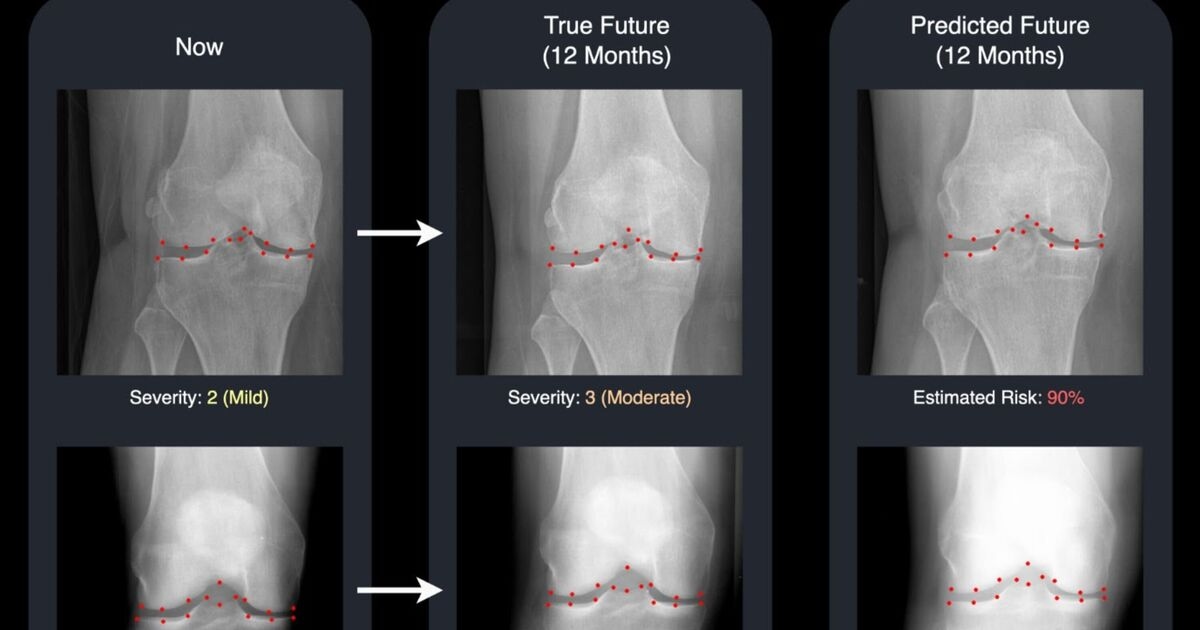

Now, a new study by the University of Surrey shows their own developed technology uses advanced machine learning to generate a realistic "future" X-ray alongside a risk score for disease progression in the knee. These two outputs combined can give doctors and patients a clear, visual forecast of how the condition may develop over time.

Using an advanced generative model, called a diffusion model, the Surrey system generates a "future" version of a patient’s knee X-ray and highlights 16 key points in the joint.

These points add transparency by showing which areas the AI is monitoring for changes, making the system easier for clinicians to understand and trust.